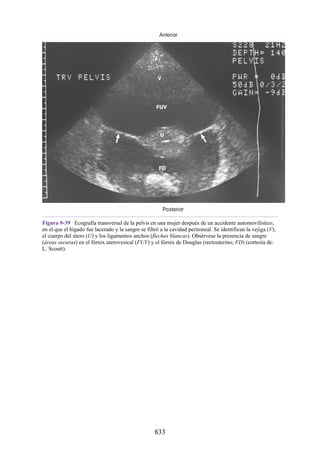

subcostal, donde se infiltra el anestésico local alrededor del nervio. El orden de las estructuras

alojadas en el haz neurovascular, de arriba hacia abajo, es el siguiente: vena, arteria y nervio